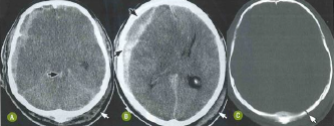

Paciente de 26 anos foi vítima de acidente automobilístico com traumatismo cranioencefálico. Nas imagens tomográficas a seguir, pode-se observar

Enunciado 4535183-1